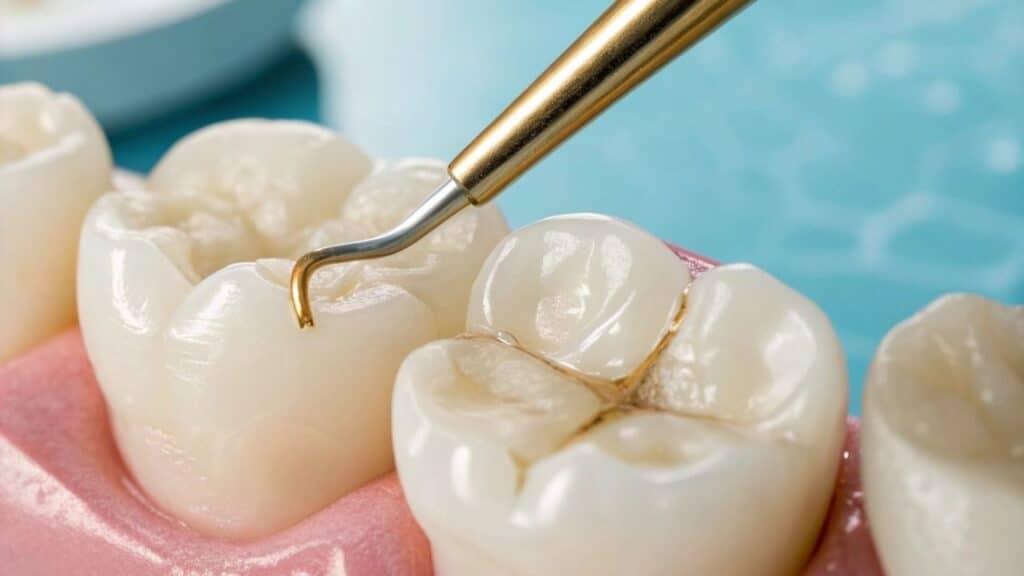

We use modern tools and magnification to clean the tooth thoroughly and ensure it’s sealed securely for long-lasting protection.